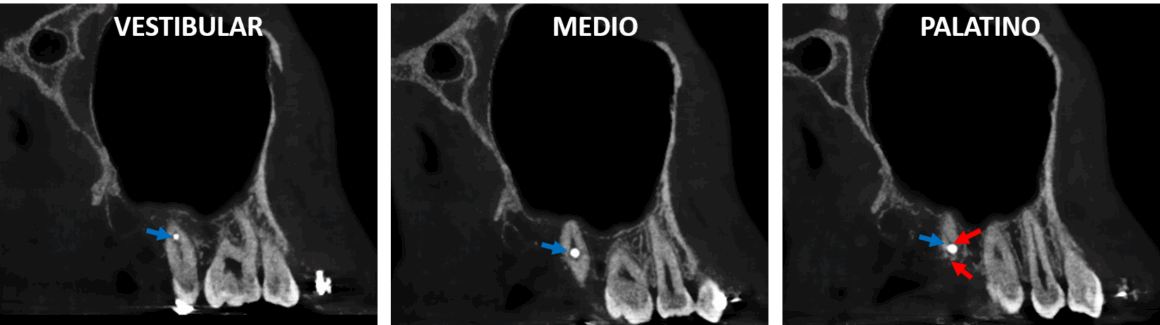

En la radiografía panorámica (Fig.1) se observa aparatología fija para ortodoncia en el maxilar superior y en la mandíbula, ausencia de terceros molares superiores e inferiores y la mordida abierta anterior. Nótese la presencia de dispositivos de osteosíntesis proyectados sobre la porción radicular de los segundos molares superiores (flecha azul).